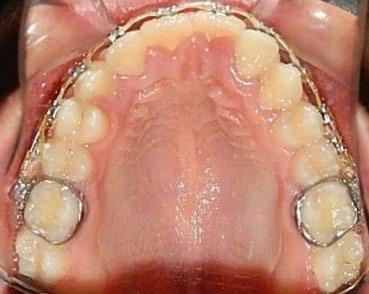

En los estudios intraorales, las fotografías iniciales muestran clase I canina y molar bilateral, mordida anterior abierta, apiñamiento leve superior e inferior, y líneas medias dentales

desviadas. En las Figuras 4, 5 y 6 se observa la forma de las arcadas superior e inferior.

Figura 6. Oclusal superior e inferior de inicio.